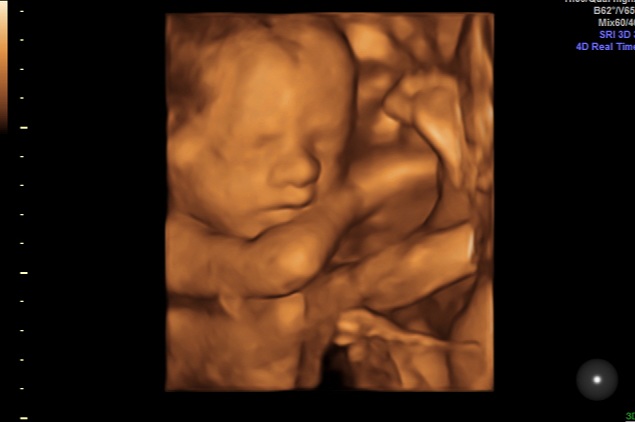

26 недель УЗИ вес двойни

Вес двойни нам 26.1 неделе: 1 плод 880гр, 2 плод 964гр. ШМ 39 мм